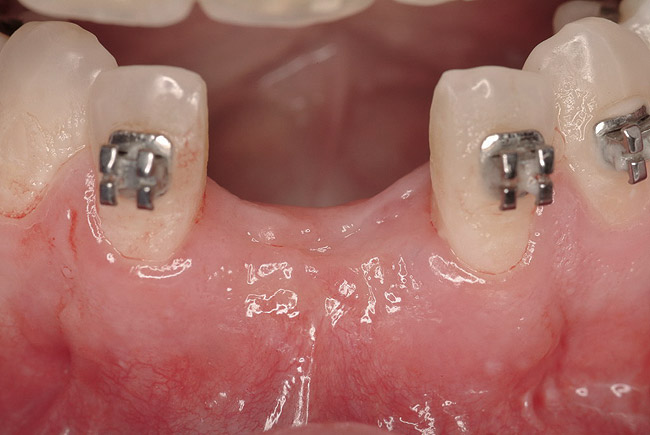

Figure 21  Five months after sinus and ridge augmentation healthy soft tissues were evident and the maxillary ridge was symmetric in the anterior sextant, where one side was originally deficient in ridge width.

Figure 21